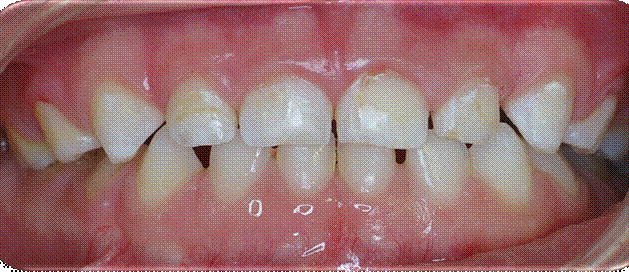

CIRUGÍA Y ORTODONCIA: Liberación de caninos retenidos

Radiografías pre-operatorias

Cementado de botones con alambre de tracción Colgajo reposisonado con suturas individuales